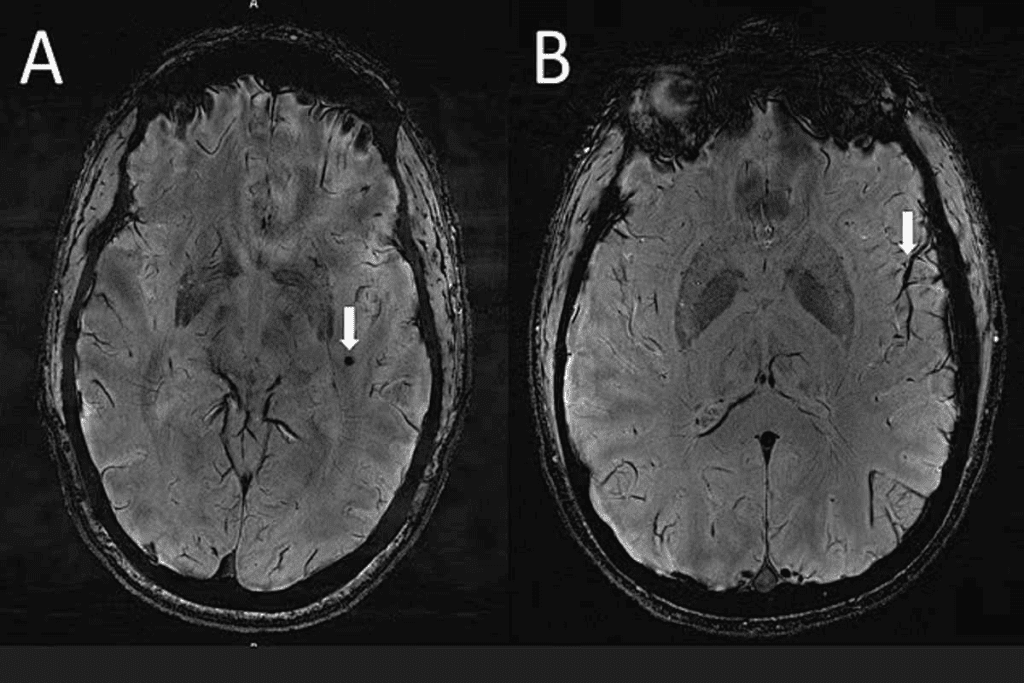

White matter lesions harm the brain’s white matter. This area has myelinated nerve fibers. These issues can come from aging, high blood pressure, or diseases like multiple sclerosis. They might also be caused by infections, injuries, or toxins.

Characteristics of White Matter Lesions:

- Demyelination or axonal loss

- Often appear as hyperintensities on MRI

- Can be asymptomatic or cause cognitive and motor symptoms